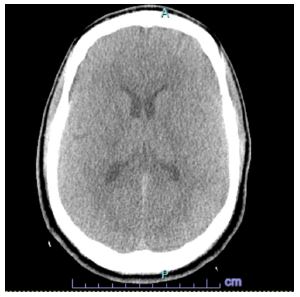

In the ED the patient denied any current symptoms and the physical exam was negative for any acute neurological findings with an NIHSS of 0. The patient’s parents at bedside endorsed dysarthria prior to arriving in the ED. A code stroke was initiated in the ED and a CT Head and CT angiogram were taken, both with unremarkable findings (Figures 1 & 2). Shortly after, the patient experienced another episode of dysarthria lasting for less than five minutes, to which a second code stroke was called and a perfusion CT was taken, showing increased Tmax in the left occipital lobe (Figure 3). Patient was transferred to the ICU for tenecteplase administration and observation with serial neurovascular checks and consults from neurology, cardiology, infectious disease.

Figure 1: CT head.